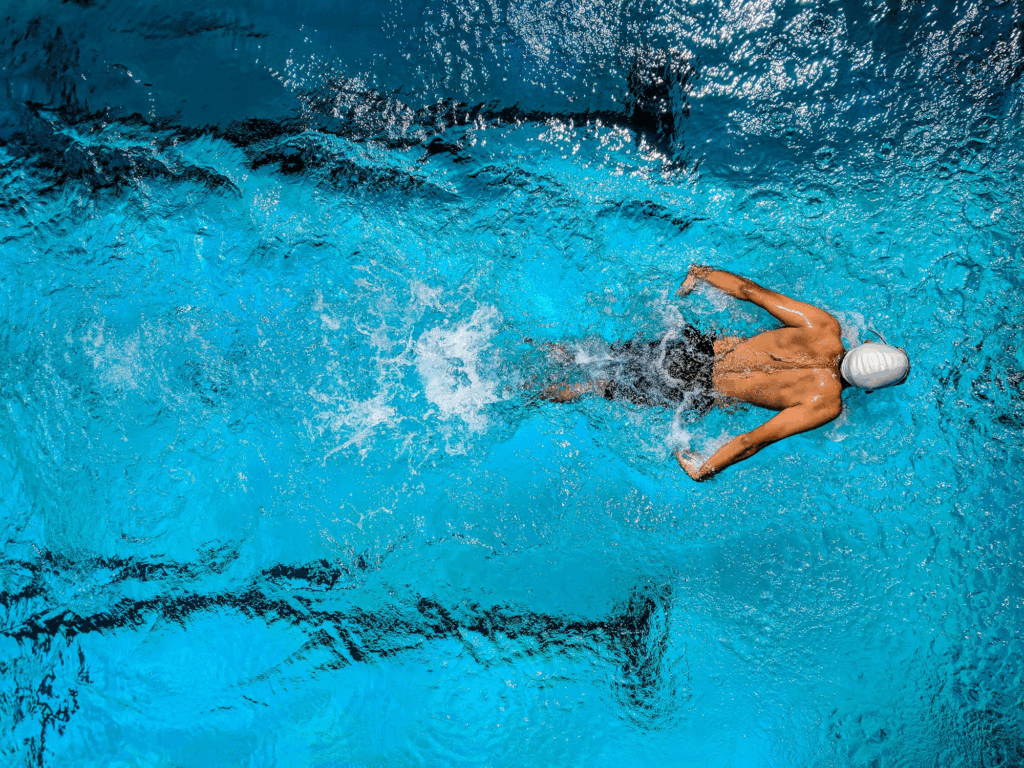

Sumado a lo mencionado, también existe una creciente atención hacia intervenciones que integran cuerpo y mente. El ejercicio físico regular, por ejemplo, ha mostrado un impacto positivo sobre los niveles de ansiedad. El yoga, la respiración diafragmática y la meditación de atención plena permiten trabajar el hiperalerta fisiológico que caracteriza a muchas personas con este cuadro. Siendo la idea central restablecer una conexión más segura con las propias sensaciones corporales, desactivando así el circuito de anticipación catastrófica.

Por si fuera poco, la actividad física tiene un efecto clínicamente significativo en la mejora del estado anímico. Siendo incluso comparable —o superior en algunos casos— a los tratamientos psicológicos y farmacológicos de primera línea, especialmente en poblaciones con sintomatología leve a moderada (Singh et al., 2023).